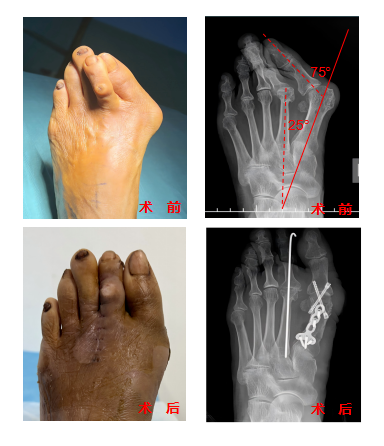

1. 医学定义:第一跖趾关节向外偏斜>15°,伴随大脚趾内侧骨赘形成。

晚期表现:第二趾叠压、行走剧痛

处理方法:需手术干预